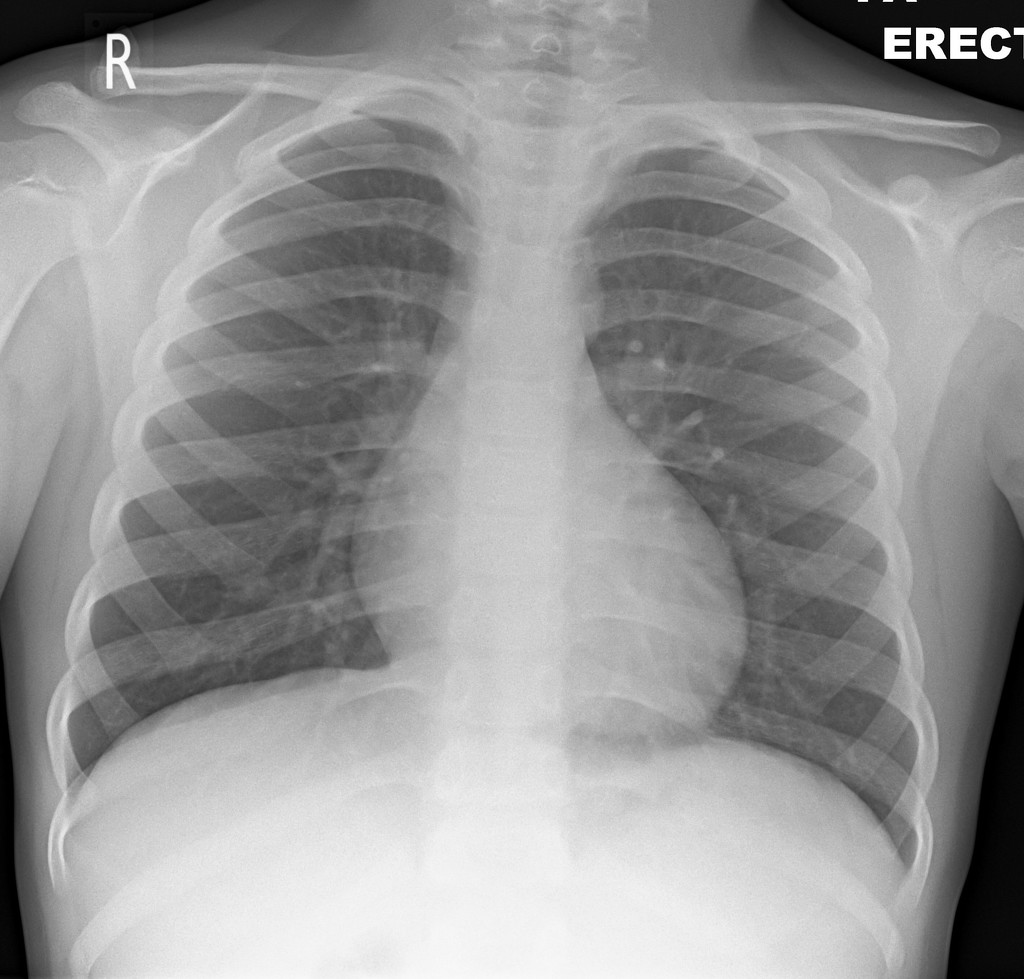

Elliot, a seven-year old boy, is brought to the emergency department after six days of fever and lethargy. He has a rash, diarrhea and decreased urine output. Both his parents are healthcare workers with possible COVID-19 exposures.

A 7-year old boy has suspected COVID-19 with multisystem inflammatory syndrome. He presents moderately unwell, but gets progressively sicker in the resuscitation bay, going into cardiogenic shock. This must be treated with careful fluid resuscitation, and eventually vasopressors. A novel option for push-dose vasopressor is explored. Cardiology and PICU should be involved early in the case.